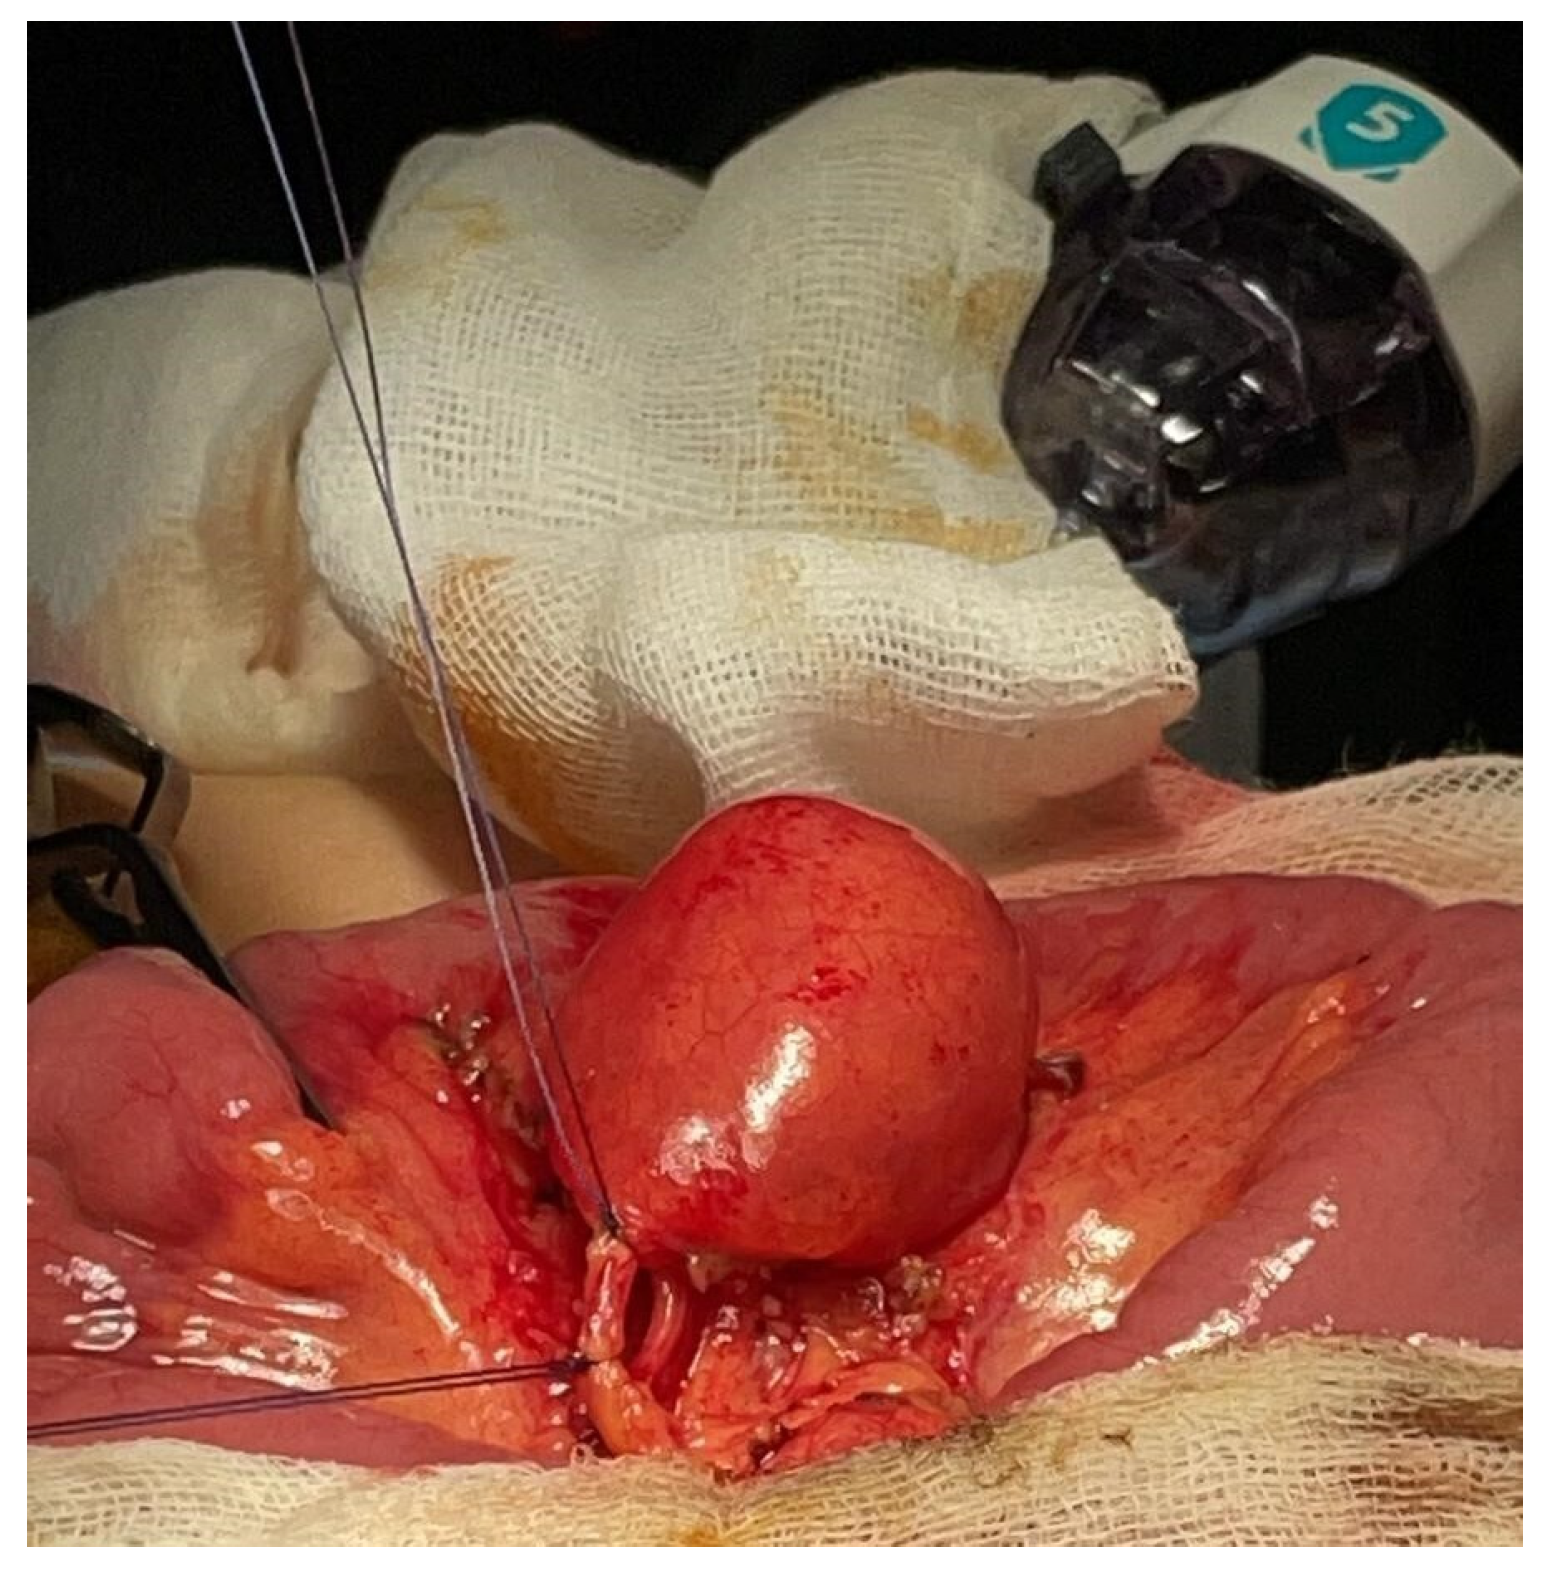

Figure 2.

Case 1—Intraoperative appearance of MMD.

Figure 3.

Case 1—MMD artery ligation.